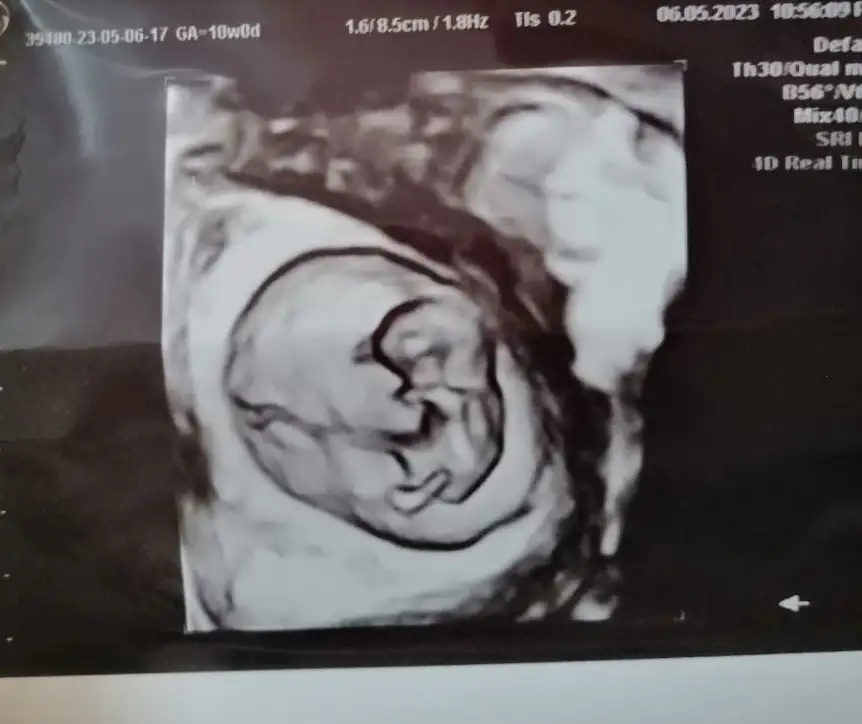

Evet kadın doğum doktoru baktı canım , damar genişlemesi olabilir. Belki bir yara vardı o kanama yapmış olabilir , Corasprin kaynaklı olabilir , üstüne görme olabilir dedi, ama alanda hiç bir kanama görmedi hatta bebişin gelişimi de 3gün ilerde imiş .